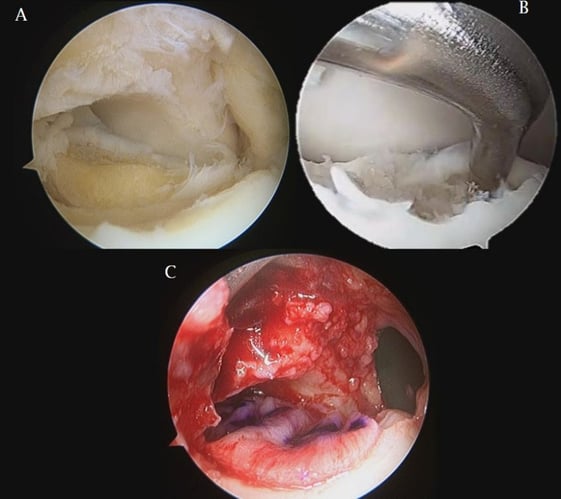

- La rigenerazione si preoccupa di utilizzare delle tecniche biologiche e di medicina rigenerativa volte a rigenerare la cartilagine laddove non era presente.

- La riparazione invece si occupa di andare a restituire una ritrovata stabilità a frammenti cartilaginei distaccati parzialmente o del tutto distaccati. Definiamo queste tecniche con la sigla LDFF (Lift: solleva il segmento patologico, Drill: stimola osso sotto il frammento patologico, Fill: riempi il difetto osseo, Fix: stabilizza il frammento cartilagineo distaccato).

Quando e come si ricorre alla rigenerazione

Per le lesioni dove la cartilagine è assente o degenerata, l'obiettivo è produrre nuovo tessuto. Le microperforazioni e le nanoperforazioni richiamano cellule staminali dal midollo osseo verso la superficie articolare e per lesioni inferiori a 0,7 cm sono spesso sufficienti.

Per lesioni più grandi o profonde, si aggiunge una membrana collagenica biologica, che guida le cellule richiamate, producendo un tessuto molto più vicino alla cartilagine originale.

La tecnica AT-AMIC, sviluppata e pubblicata dal nostro gruppo nel 2015, rappresenta oggi l'applicazione artroscopica di questo principio, eseguibile in modo mininvasivo.

Un approccio innovativo differente è la tecnica Minced-Cartilage (Autocart). Questa tecnica, che il mio gruppo esegue artroscopicamente, prevede il prelievo dei frammenti danneggiati di cartilagine, la loro aspirazione ed attivazione fuori dal corpo con esposizione associata ad enzimi e PRP. Il tessuto così ottenuto ha un aspetto denso che consente la sua reintroduzione a sostituire il difetto in artroscopia.

Il mio algoritmo prevede tecnica Minced Cartilage (Autocart) per le lesioni inferiori al centimetro di diametro, la tecnica At-Amic per le lesioni maggiori con possibile associazione di tecnica Minced Cartilage per rendere la ricostruzione davvero anatomica.

La riparazione per stabilizzare i frammenti distaccati

Quando esiste un frammento cartilagineo parzialmente o completamente distaccato, l'obiettivo è fissarlo prima che perda la sua vitalità.

La variabile cruciale in questo caso è il tempo che intercorre fra lesione, diagnosi e trattamento. Un frammento ancora ancorato e vascolarizzato risponde in modo radicalmente diverso rispetto a uno distaccato da mesi. Questo è il motivo per cui un dolore persistente dopo una distorsione non va mai ignorato: la finestra terapeutica favorevole si chiude.

Le tecniche di riparazione prevedono la stabilizzazione artroscopica con viti riassorbibili o ancore ossee, a volte integrate con membrane biologiche o tecniche di Minced Cartilage.